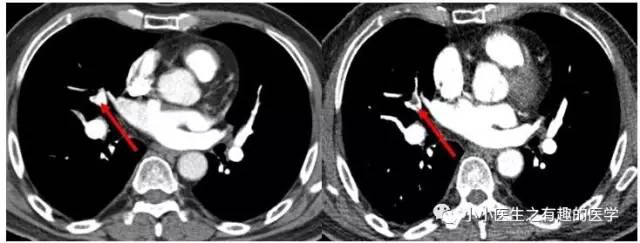

很多中国的论文图像不清楚,来个广州呼研所的研究生论文,看看各种大血栓。

左、右肺动脉均有,治疗后效果很满意。

上图治疗后,效果还可以。

上图,右肺动脉栓塞,治疗基本无效。

上图:肺栓塞治疗后,反而加重了。